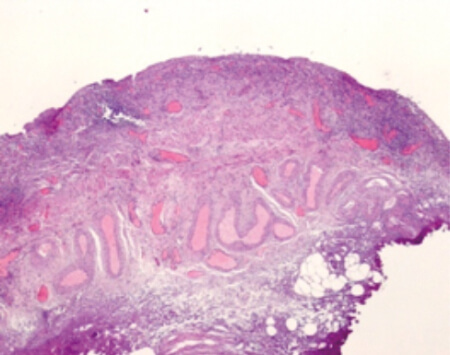

Figure 1: Urothelium demonstrating denudation of the GAG layer and infiltration with inflammatory cells.